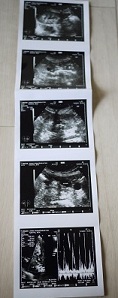

いっぱい撮ってもらったエコー。

モエさん、エコー検査はいつも大暴れなので。笑

見せられるような画像じゃないんだけど・・。そう言ってました^^;

ココの病院はエコー画像も、ちゃんっと渡してくれます。